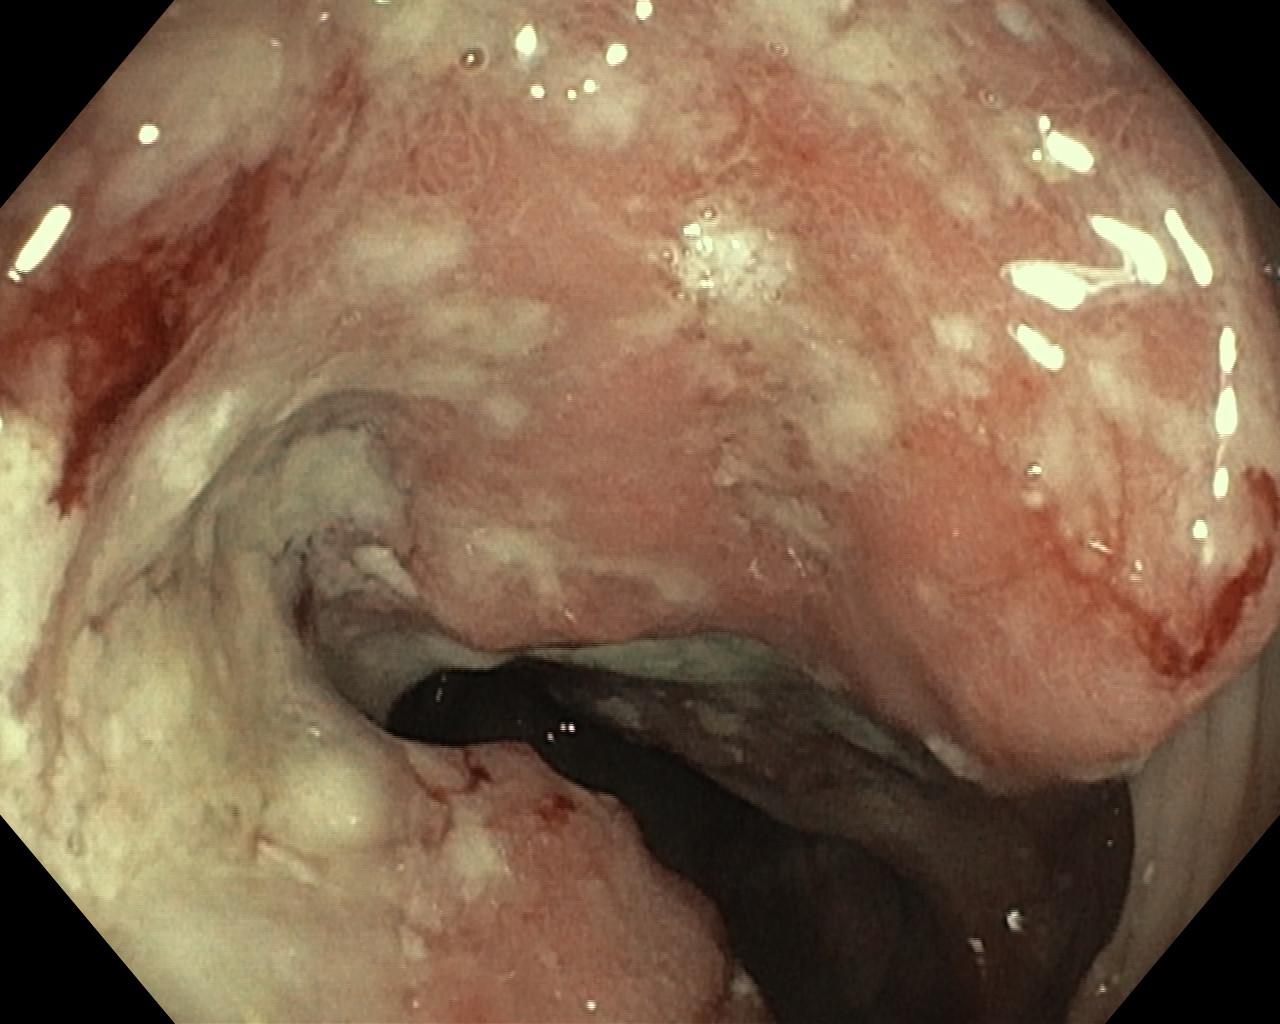

Nowotwory przewodu pokarmowego